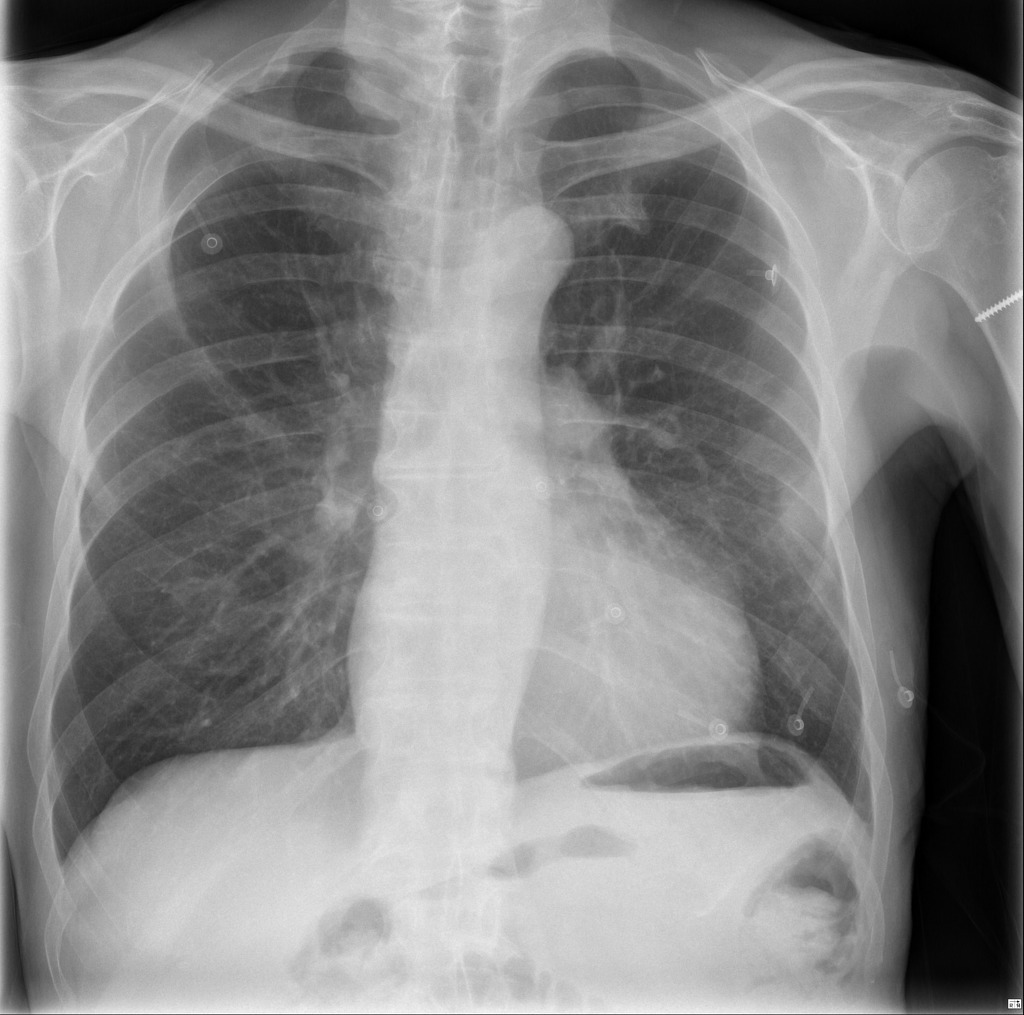

How to assess image quality

Rotation

Inspiration

Projection

Exposure